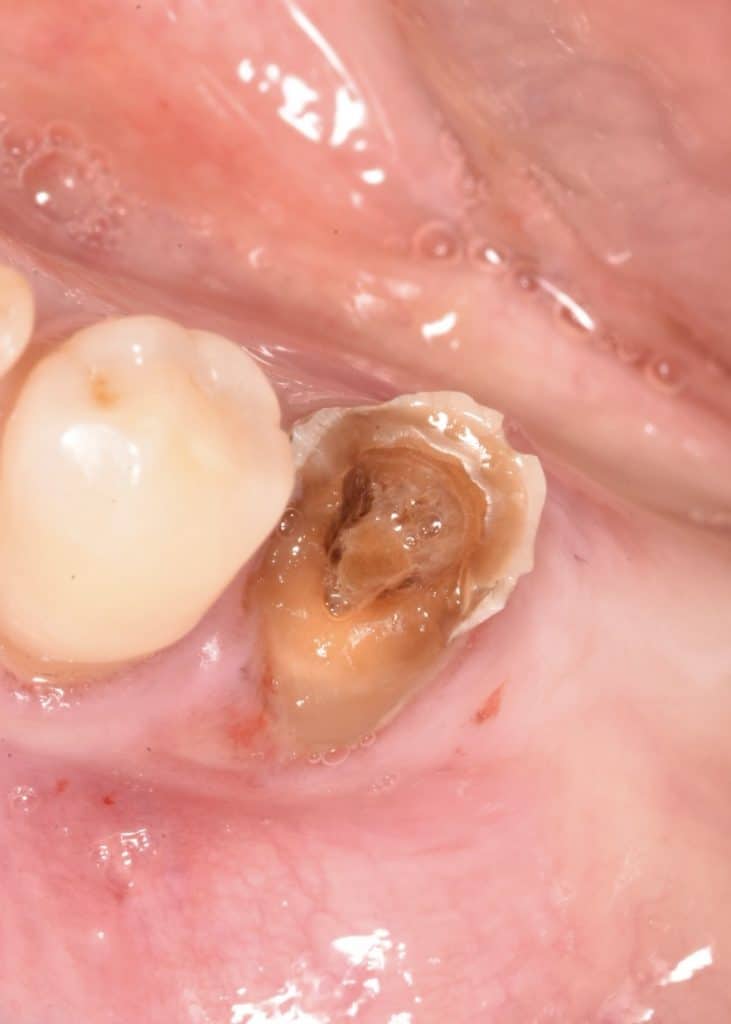

patient attended to clinic seeking for extraction his tooth no. 34

patient was educated, i convinced him to repeat his tooth to function.

⛔️ remove all caries from tooth no. 34